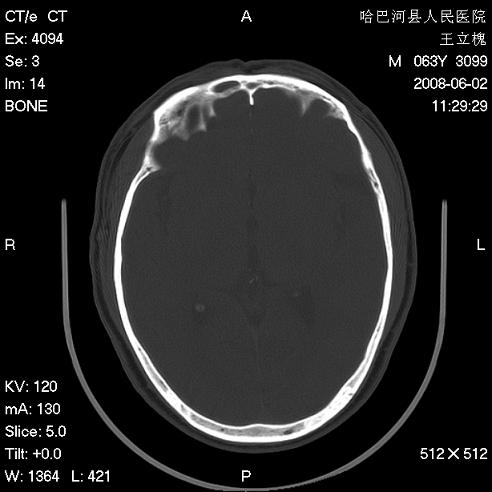

标题: CT13803:反复性鼻塞、流涕一年余 [打印本页]

标题: CT13803:反复性鼻塞、流涕一年余

1.全组副鼻窦炎2.双侧上颌窦积液

全组副鼻窦炎

.全组副鼻窦炎2.双侧上颌窦积液

1)全副鼻窦炎(左侧上颌窦黏膜下囊肿或息肉)。2)左眼眶肌锥内不规则小结节状软组织密度影;考虑为小血管瘤可能。建议行ct增强扫描检查。

全组副鼻窦炎,左侧肌锥内不规则形软组织肿块影,与眼外肌密度相当,左侧视神经受压,肿块与视神经及眼外肌分界清晰,眼外肌无增粗,眶壁无破坏,球后脂肪间隙不模糊,考虑良性改变,小血管瘤或神经源性肿瘤可能,建议增强扫描。